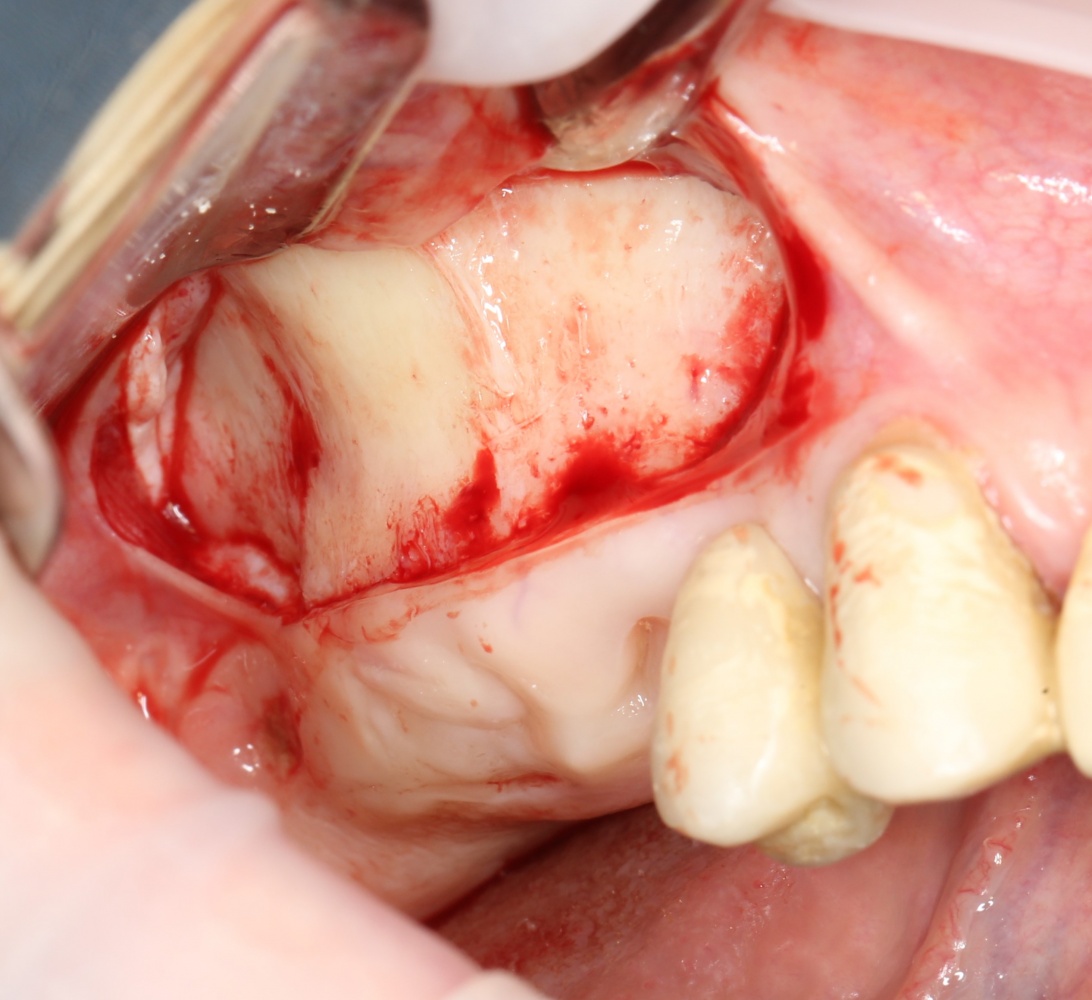

Простой синуслифтинг. Часть I.